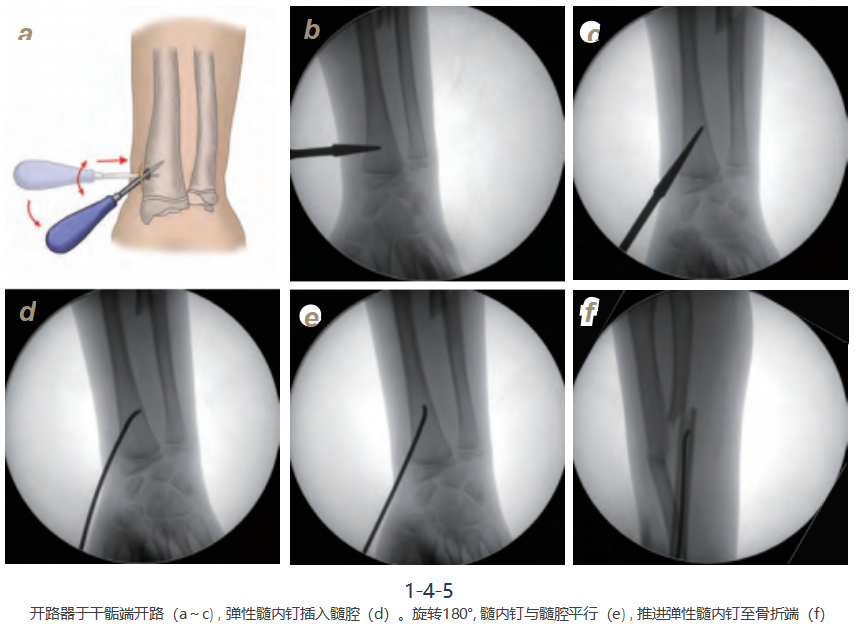

4. 弹性髓内钉置入:

垂直于桡骨远端干骺端插入开路器(图1-4-5a,b),穿透皮质后 与骨干成45°角进入,所开孔应比所选髓内钉直径略大,不要损伤骨骺板(图1-4-5c)。髓内钉尖与骨皮质垂直插入髓腔(图1-4-5d)。然后旋转180°, 使髓内钉与 髓腔平行(图1-4-5e)。如果需要,使用“C”型臂X线机检查髓内钉的位置。推进弹性 髓内钉至骨折端(图1-4-5f)。